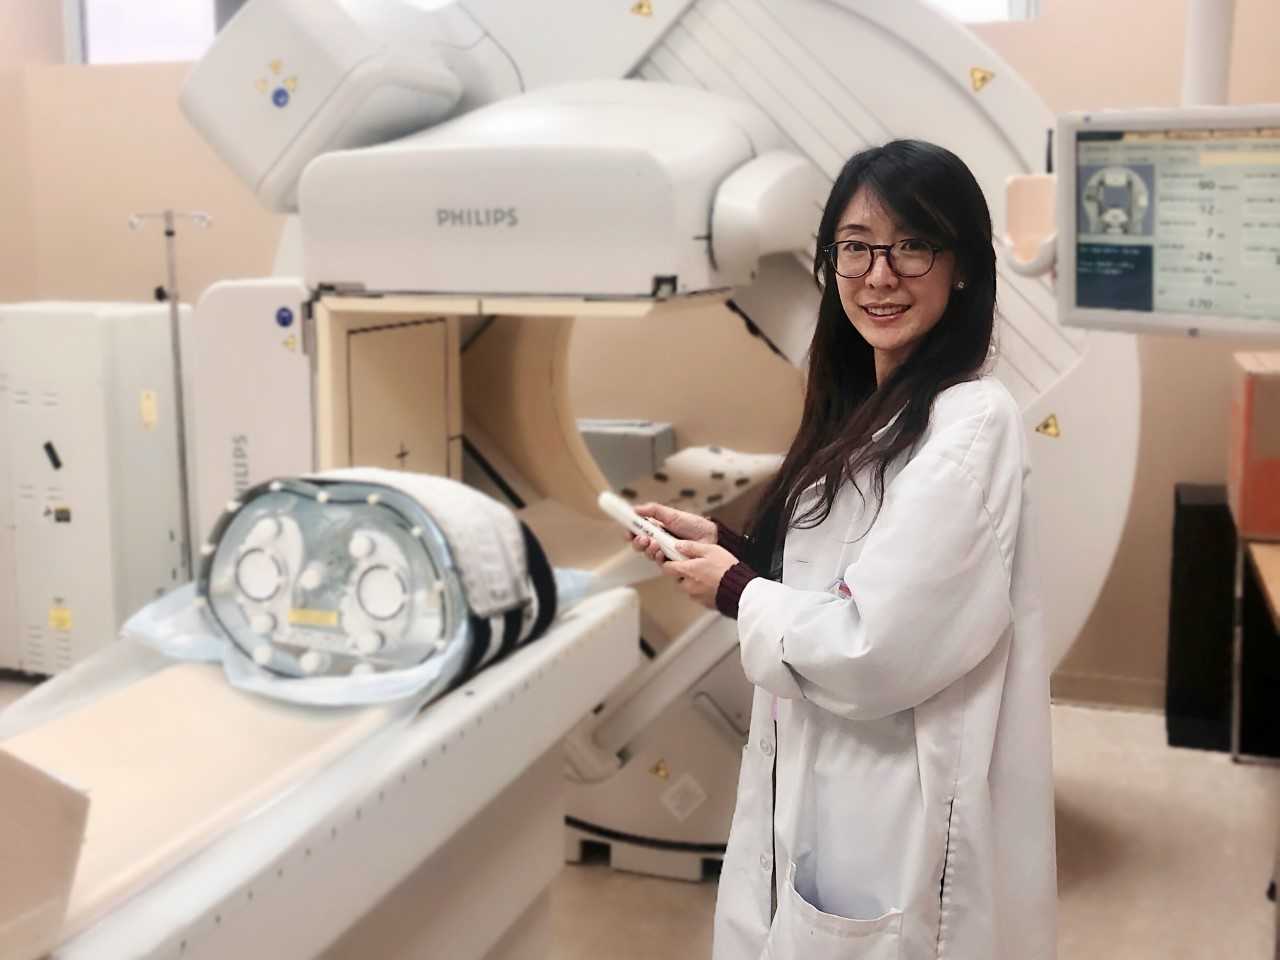

Moses Campus, along with Children’s Hospital at Montefiore Einstein, features 726 adult inpatient beds and 106 pediatric inpatient beds. The facility also offers services to outpatients. As an NCI-Designated Cancer Center, Moses provides diagnostic and therapeutic modalities through an active theranostics program. While training at Moses, residents partake in a particularly rigorous program in oncologic and non-oncologic pediatric and adult nuclear medicine. Our Transplant Center, also on-site, affords residents the ability to evaluate organ physiology pre- and post-transplant.

Our 431-bed Jack D. Weiler Hospital is located adjacent to the Albert Einstein College of Medicine in the Morris Park section of the Bronx. While at Weiler, residents participate in independent, hands-on training, with a particular focus on emergency cases and nuclear cardiology studies overseen by an attending. Residents are also exposed to much of their on-call experience at this location.